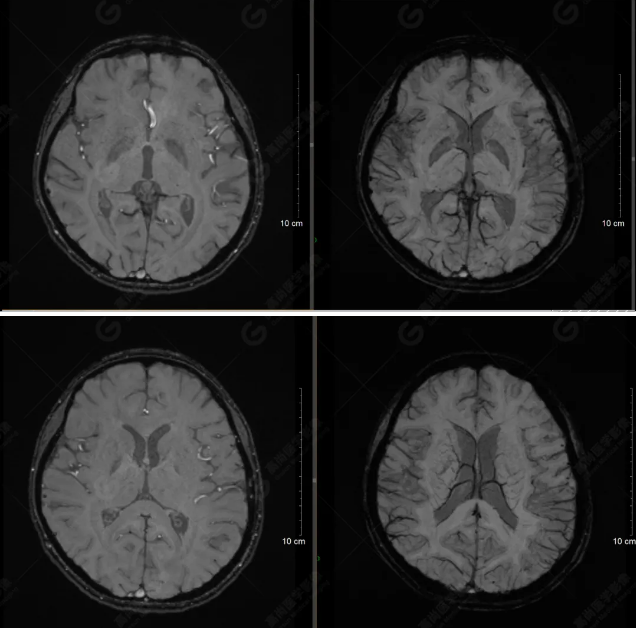

(左側(cè)為薄層原始圖像,右側(cè)為后處理5mm圖像)

SWI序列影像表現(xiàn)及診斷

左側(cè)額底及左側(cè)顳葉內(nèi)見多發(fā)斑點狀極低信號影??紤]額顳葉多發(fā)腦挫傷伴微出血、含鐵血黃素沉著,左側(cè)乳突骨折、乳突內(nèi)積血。討論:1、SWI利用不同組織間磁敏感的差異成像并將其放大,通過檢測病灶中的靜脈分布、出血灶和礦物質(zhì)沉積等,有效改善了相關(guān)疾病的診斷,主要應(yīng)用于中樞神經(jīng)系統(tǒng)。2、根據(jù)磁距圖像和相位圖像表現(xiàn),對于鑒別顱內(nèi)出血及鈣化有一定程度的價值,用于彌補(bǔ)MRI對鈣化顯示的不足。